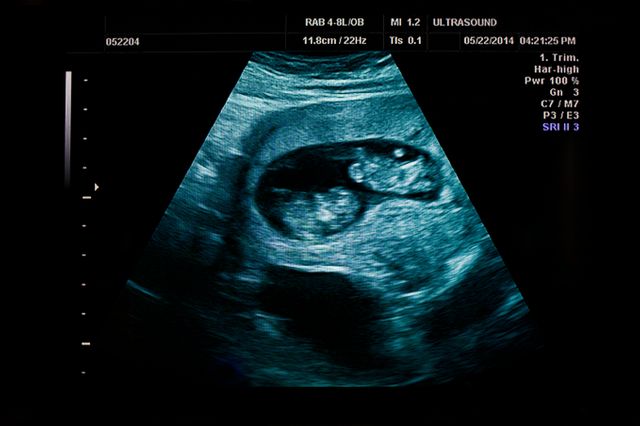

Grossesse de jumeaux. La grossesse de jumeaux implique des changements et adaptations physiques et psychiques plus complexes Pour en savoir plus sur le vécu psychologique de la femme enceinte, nous avons interrogé Stéphanie Staraci, psychologue à l'Institut de Puériculture de Paris Lire notre article. Seule l’échographie pourra confirmer que vous attendez des jumeaux C’est lors de la première échographie (entre 11 et 13 SA) également appelée échographie de datation que vous apprendrez la bonne nouvelle. Aujourd’hui, on réalise des examens par ultrasons dès les premiers jours de la grossesse On est donc en mesure de détecter les grossesses gémellaires ou multiples dès le premier trimestre de la grossesse Mais il arrive qu’une échographie suivante révèle un changement on ne perçoit plus le battement du cœur d’un des jumeaux.

Avoir des jumeaux la différence entre les vrais et les faux jumeaux Quand on parle de grossesse gémellaire, il est essentiel de distinguer les vrais jumeaux des faux jumeaux Au moment de la fécondation, si l’ovule est unique et qu’il est fécondé par un spermatozoïde, il peut produire deux embryons par division. Le suivi de grossesse Le médecin peut se douter que la mère attend des jumeaux quand il procède à l’examen physique Les femmes qui portent des jumeaux ont habituellement un utérus plus large Par ailleurs, lorsque le médecin écoute le cœur du bébé avec un appareil Doppler, il peut entendre 2 rythmes cardiaques différents. Surtout pour retarder cela ne devrait pas être les futures mères qui portent des jumeaux Surveiller la dynamique du contenu dans le sang de cette hormone devrait être pendant toute la période de la grossesse À chaque traitement, le médecin établit un plan détaillé des tests à effectuer sur une femme portant plusieurs bébés à la fois.